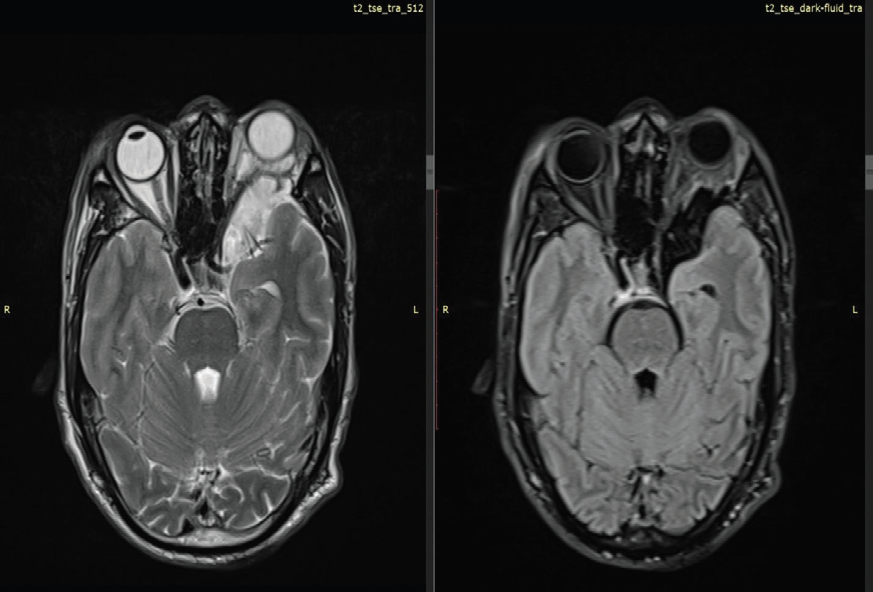

MRI of the brain and orbits with contrast demonstrated hypoplasia of the left sphenoid wing with herniation of brain parenchyma and CSF into the superior aspect of the left orbit, consistent with a left

Figure 1: MRI brain, axial T2-weighted image OF 39-YEAR-OLD

GENTLEMAN WITH KNOWN NF-1 demonstrates prominent arachnoid

spaces in the left anterior temporal region, secondary to the orbital

encephalocele. There is compression and medial deviation of the left optic

nerve without abnormal enhancement, excluding optic nerve glioma or optic

nerve sheath meningioma. There is severe narrowing of left superior orbital

fissure and compression of optic nerve at this level.

orbital encephalocele. This resulted in left-sided proptosis with

compression and mild medial deviation of the intraorbital segment

of the left optic nerve. Marked narrowing of the left superior orbital

fissure was noted, with optic nerve compression at this level.

Prominent arachnoid spaces were seen in the left anterior temporal region secondary to the encephalocele, with medial displacement of the left middle cerebral artery. No abnormal enlargement or postcontrast enhancement of the optic nerve was identified, effectively excluding optic nerve glioma and optic nerve sheath meningioma. Additional findings included multiple scalp neurofibromas and T2/FLAIR hyperintense foci involving the bilateral thalami and periventricular regions, consistent with focal areas of signal intensity (FASI). The left sphenoid sinus was hypoplastic.